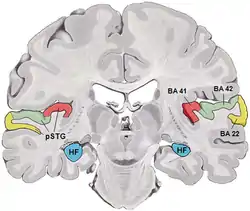

Lateral view of human cerebrum. BA41 and 42 shown in red. | |

Brodmann areas 41 and 42 are parts of the primary auditory cortex.

Brodmann area 41 is also known as the anterior transverse temporal area 41 (H). It is a cytoarchitectonic division of the cerebral cortex occupying the anterior transverse temporal gyrus (H) in the bank of the lateral sulcus on the dorsal surface of the temporal lobe. Brodmann area 41 is bounded medially by the parainsular area 52 (H) and laterally by the posterior transverse temporal area 42 (H) (Brodmann-1909).

Brodmann area 42 is also known as the posterior transverse temporal area 42 (H), and is also a subdivision of the temporal lobe. Brodmann area 42 is bounded medially by the anterior transverse temporal area 41 (H) and laterally by the superior temporal area 22 (Brodmann-1909).

Brodmann areas 41 and 42 are parts of the primary auditory cortex. This is the first cortical destination of auditory information stemming from the thalamus. Neural activity in this brain part corresponds most strongly with the objective physical properties of a sound.

BA41. BA42

BA42 BA41. Inside lateral sulcus.

BA41. Inside lateral sulcus. BA42. Inside lateral sulcus.